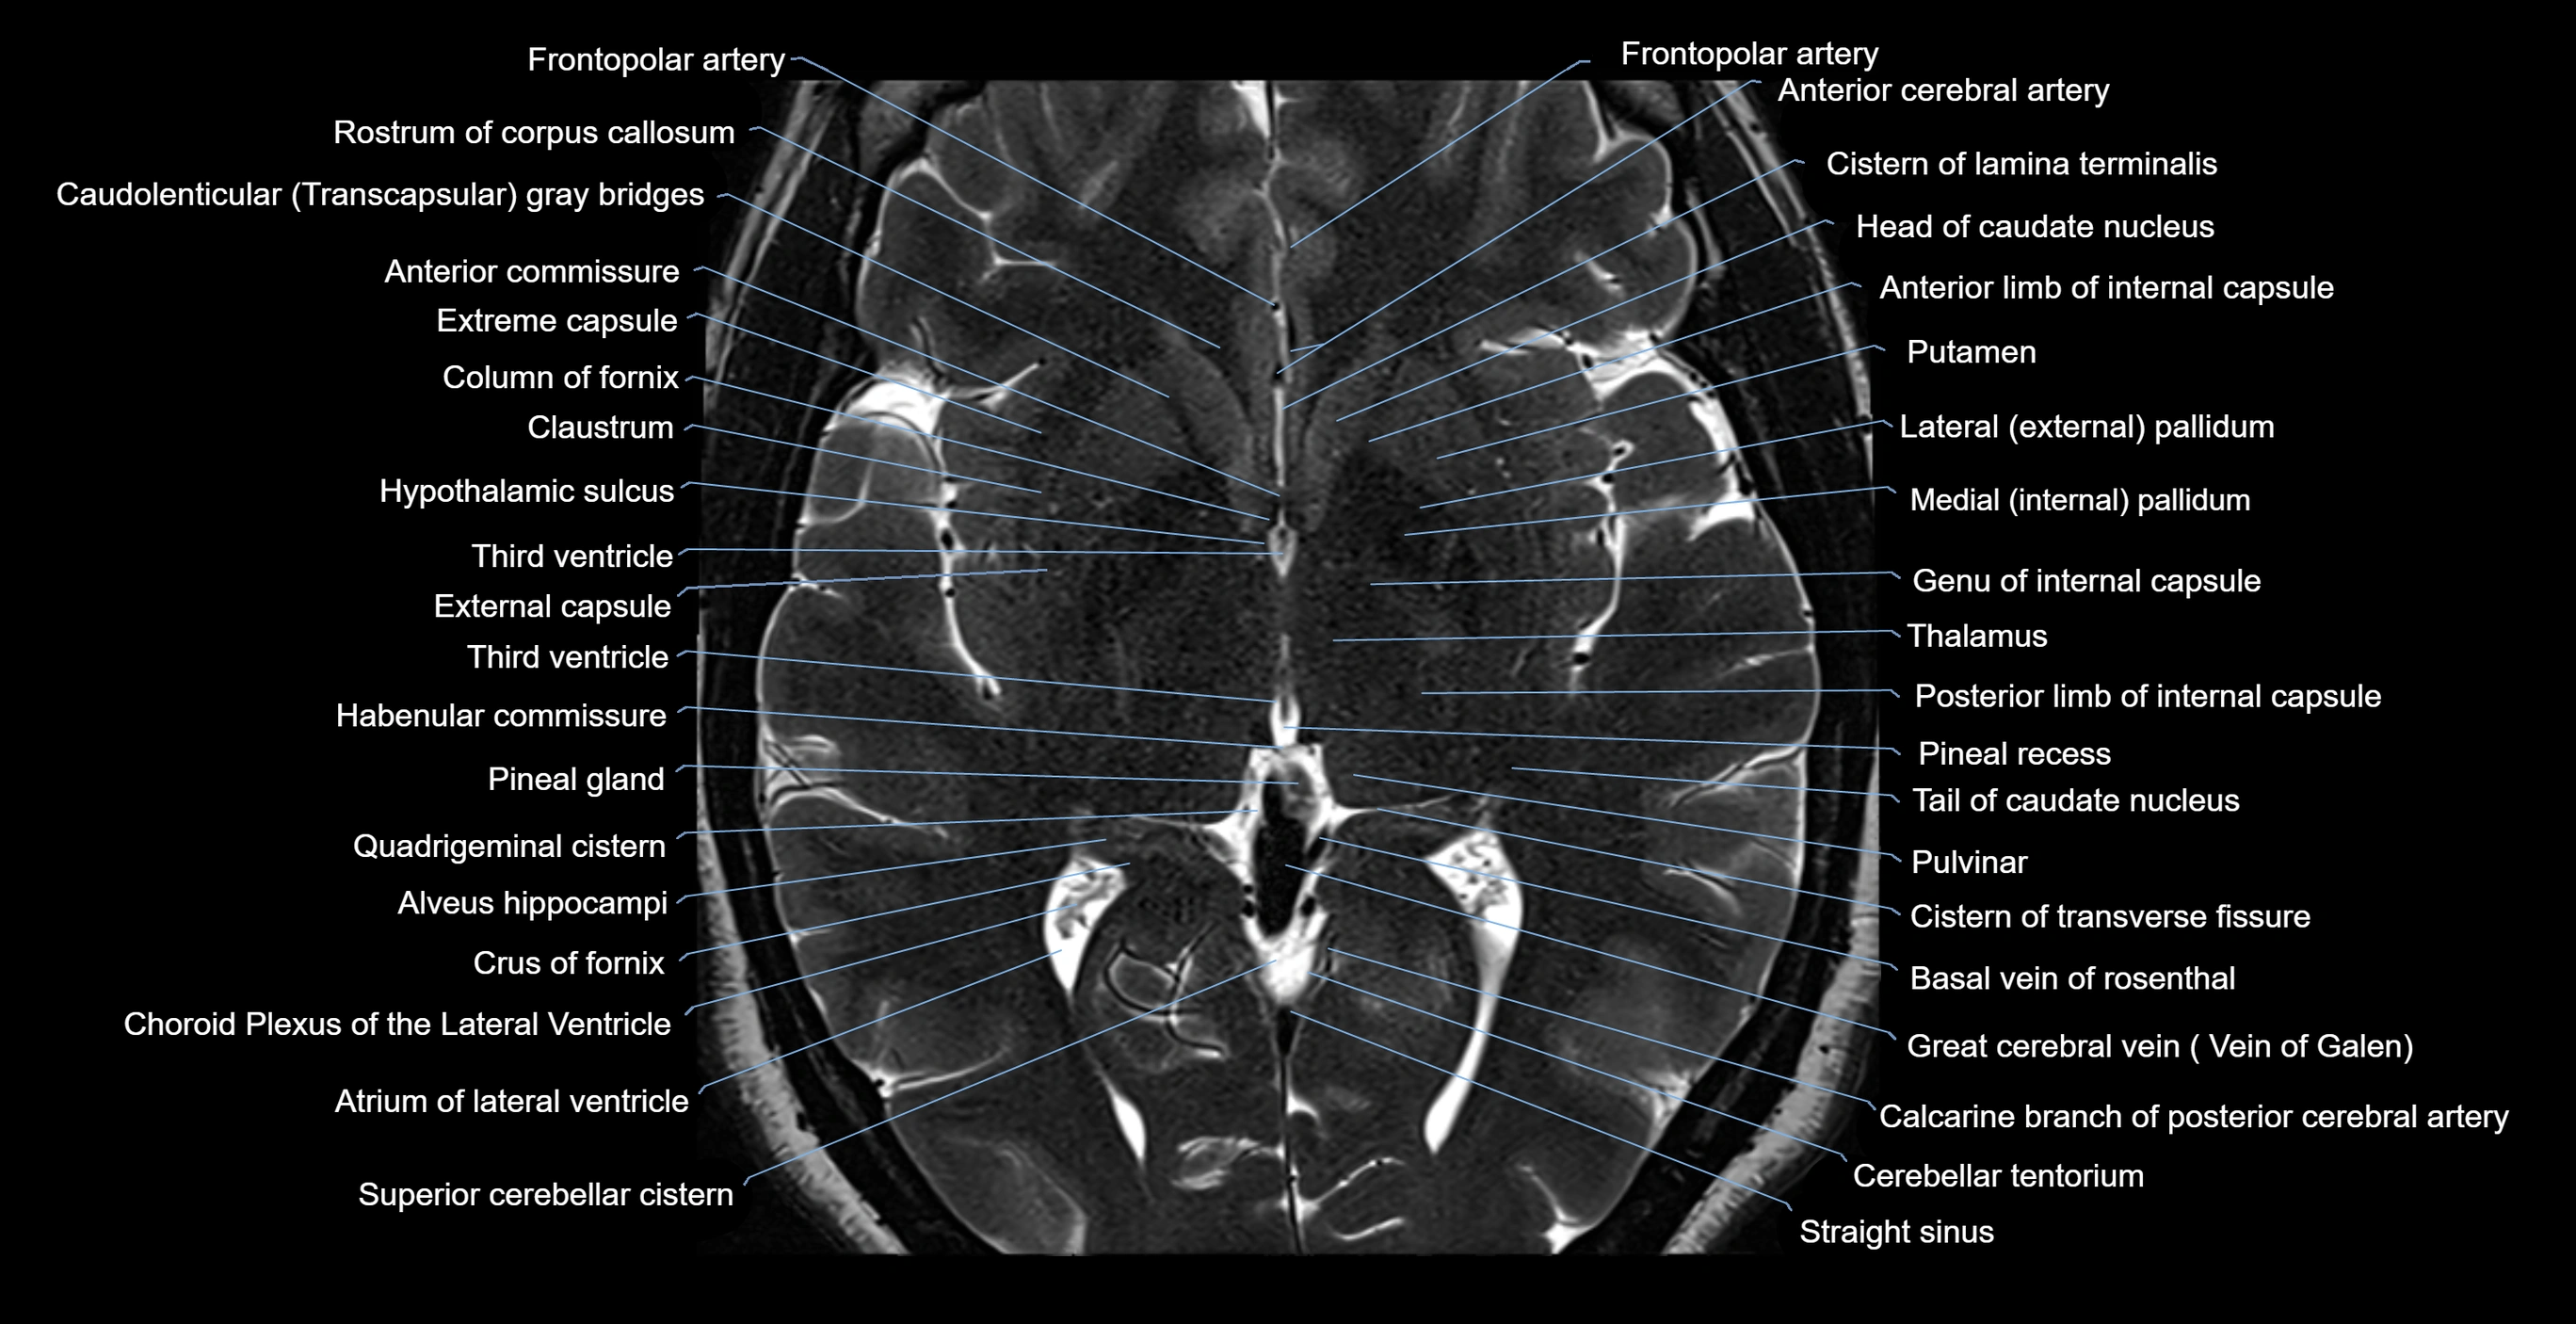

MRI images